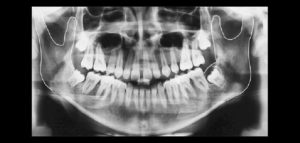

El conocimiento de la bifurcación del conducto dentario inferior (CDI) es importante, ya que ofrece posibles explicaciones para el fracaso de la anestesia, y para